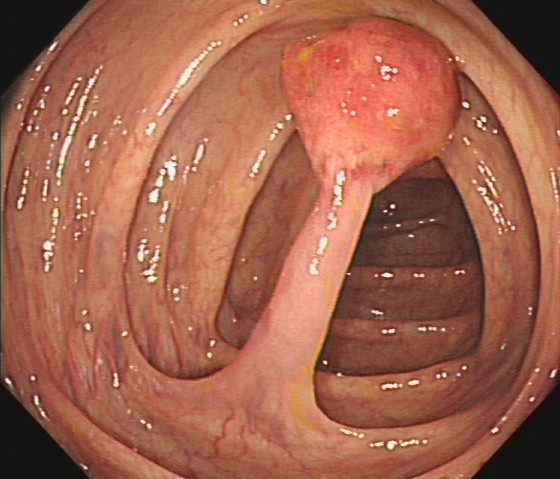

陈先生(44岁,乙状结肠息肉,图2)

肠镜一照,息肉现形!形态各异的大肠息肉,离癌有多远?(图2)

图2

病理诊断:(乙状结肠)管状腺瘤,局灶癌变-黏膜内癌(腺癌),脉管未见癌栓,蒂未见累及。

解读:这是从腺瘤发展成癌的典型案例。“局灶癌变”指息肉中只有一小部分区域发生了真正的癌变。“黏膜内癌”指癌细胞仍局限于黏膜层内,尚未穿透黏膜肌层向更深层浸润。脉管无癌栓、蒂部未累及是非常积极的信号,表明癌细胞尚未通过血管/淋巴管扩散,也未侵犯息肉蒂部。此时完整切除息肉,很大可能达到根治效果。距离进展期癌:非常近,但尚属极早期,原位癌/粘膜内癌。